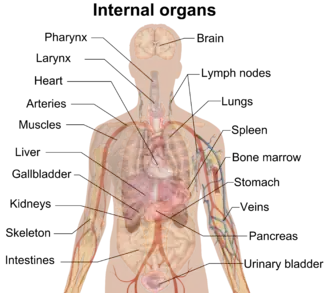

The human body consists of biological systems, that consist of organs, that consist of tissues, that consist of cells and connective tissue.

Internal organs (by region)

Head and neck

- Eyes (2)

- Pineal gland

- Pituitary gland

- Thyroid gland

- Parathyroid glands (4)

Thorax

Abdomen and pelvis (both sexes)

- Adrenal glands (2)

- Appendix

- Bladder

- Gallbladder

- Large intestine

- Small intestine

- Kidneys (2)

- Liver

- Pancreas – gland

- Spleen

- Stomach

Major organ systems

- Circulatory system: pumping and channeling blood to and from the body and lungs with heart, blood, blood vessels

- Digestive system: digestion and processing food with salivary glands, esophagus, stomach, liver, gallbladder, pancreas, intestines, rectum, anus

- Endocrine system: communication within the body using hormones made by endocrine glands such as the hypothalamus, pituitary gland, pineal gland, thyroid, parathyroid glands, adrenal glands

- Immune system: the system that fights off disease; composed of leukocytes, tonsils, adenoids, thymus, spleen

- Integumentary system: skin, hair, nails

- Lymphatic system: structures involved in the transfer of lymph between tissues and the blood stream, the lymph and the nodes and vessels that transport it

- Musculoskeletal system: muscles provide movement and a skeleton provides structural support and protection with bones, cartilage, ligaments, tendons

- Nervous system: collecting, transferring and processing information with brain, spinal cord, nerves

- Reproductive system: the sex organs; in the female; ovaries, fallopian tubes, uterus, vagina, mammary glands, and in the male; testicles, vas deferens, seminal vesicles, prostate, penis

- Respiratory system: the organs used for breathing, the pharynx, larynx, trachea, bronchi, lungs, diaphragm

- Urinary system: kidneys, ureters, bladder, urethra involved in fluid balance, electrolyte balance, and excretion of urine